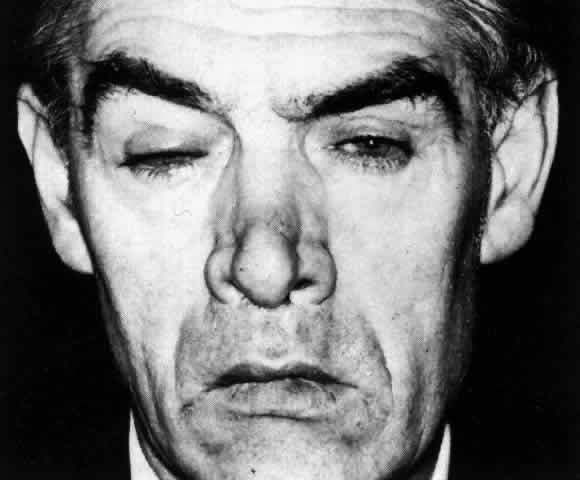

of the eye. A posterior scleritis often occurs as an extension of anterior

disease; but, as in Figure 20, most of the inflammation (in some cases all of the inflammation) is in

the posterior segment and the exudative detachments and subretinal granulomas

Fig. 20. Posterior scleritis. This eye was removed because of loss of vision and

pain, mistakenly diagnosed as malignant melanoma. (Courtesy of Professor N. Ashton) Fig. 20. Posterior scleritis. This eye was removed because of loss of vision and

pain, mistakenly diagnosed as malignant melanoma. (Courtesy of Professor N. Ashton)